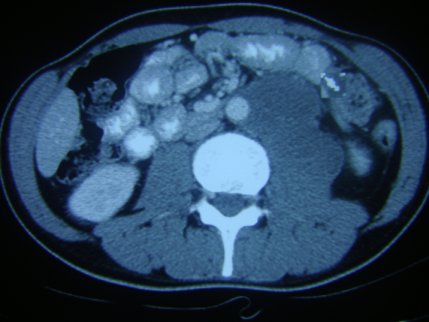

【111-1 醫學(五) 第74題】下圖為中年男性所呈現的後腹膜腔腫瘤,最不可能的診斷為:

這題的解題核心在於判斷哪種腫瘤「最不可能」出現在後腹膜腔,特別是考慮到腫瘤的來源和轉移特性。圖片顯示一個巨大的後腹膜腔腫瘤,但關鍵在於選項B所指的腦部原發腫瘤極少轉移到腦部以外。